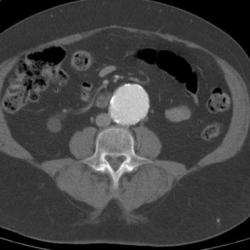

CT scanning accurately demonstrates dilation of the aorta and involvement of major branch vessels proximally and distally. This information helps in determining the appropriate intervention, which may be either surgical or endovascular repair. (See the image below.)

In the United States, 15,000 deaths per year are attributed to abdominal aortic aneurysms (AAAs). Abdominal aortic aneurysms occur most commonly in individuals between 65 and 75 years of age.

AAA is thought to be a degenerative process of the aorta, the cause of which remains unclear. It is often attributed to atherosclerosis because these changes are observed in the aneurysm at the time of surgery.

AAAs arise as a result of a failure of the major structural proteins of the aorta (elastin and collagen). The inciting factors are not known, but a genetic predisposition clearly exists.